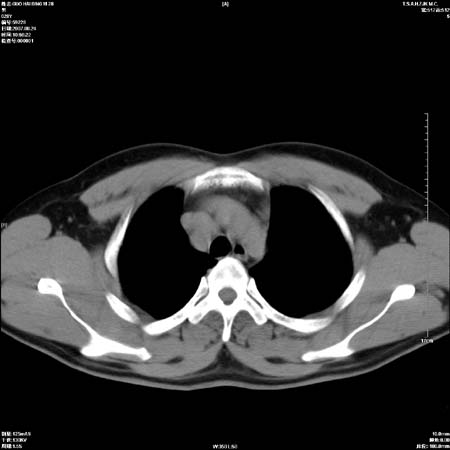

男性,28岁,体检发现左肺病变,患者只有背部隐痛感,哀哉,真不忍心下诊断啊。

左肺门区软组织肿块,左肺上叶支气管开口消失,纵隔内见肿大淋巴结,考虑左中心型肺部,可以做纤支镜取病理确认.

左肺肺门区肿块影,分叶明显:诊断肺癌应该没有疑问。

本例倾向周围型肺癌

鉴别:中央型肺癌-肿块那么明显一般合并节段肺不张或阻塞性炎症。

本例肿块边缘外侧可见左上叶各段支气管。

左肺肺门区肿块影,分叶明显,左肺上叶支气管开口受压,纵隔内见肿大淋巴结,考虑左中心型肺癌。

左侧肺门区见一块状病灶可见分叶,纵隔内及左肺门见肿大淋巴结,应该是周围型肺癌而不是中心型肺癌,原因有以下2点,1未见阻塞肺气肿和阻塞性炎症,这么大肿块如果是中心型肺癌就是未分化型或小细胞型肺癌不出现阻塞性肺不张也应该有阻塞炎症或阻塞性肺气肿,2如果是中心型肺癌临床出现最早的症状是咳嗽(此时可无任何异常影象),而此人这么大肿块只有背部隐痛是体检才发现无法解释.

肿块形态影像支持左上叶中央型肺癌伴纵隔淋巴结转移。

左肺门区分叶状软组织肿块,纵隔内有肿大淋巴结,诊断肺癌应该问题不大。